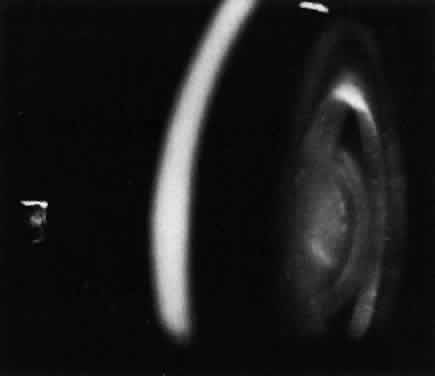

A unique retinal abnormality, the macular halo syndrome, has been reported in type B NPD by Cogan and Kuwabara135 and consists of a ring of opacities around the macula that causes no visual impairment (Fig. 15). This abnormality has been reported by several authors.141–143The crystalloid halo which measures about half the disc diameter occurs at the outer edge of the retina mainly in Henle's fiber layer causing only minor obstruction of the overlying vessels. Matthews and associates144 proposed that the macular halo represents the mildest form of a cherry-red spot in the ganglion cell layer of the retina. Their findings are in conflict with those of Cogan et al.138 The precise location of the opacities in the retina remains uncertain because of the lack of histopathology. The available clinical data suggest that such opacities are permanent.

Fig. 15. Macular halo in a patient with Niemann-Pick type B.